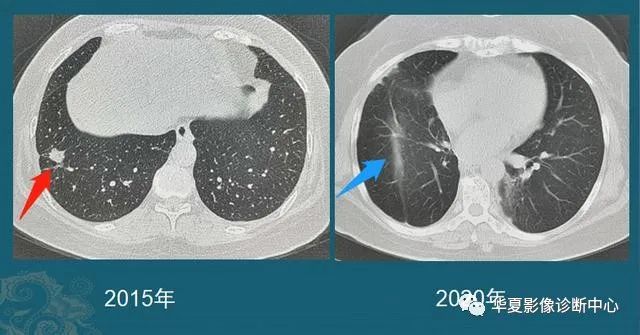

豪大夫每年都能发现很多从肺小结节长大的肺癌,挑出两个速度最快的分享一下:

图6

这位病人2016年体检还是正常的,2017年查出一个3 mm的肺结节,用了两年半时间,增长到>1 cm,手术病理是肺腺癌。

注意:这几乎是最快的一类的,很少见!所以高危人群推荐每年胸部体检一次是有益的。

图7

这是一位老年男性,有吸烟史,也是在两年多的时间内,肺结节从不足3 mm长到1 cm以上,后来病理确诊肺鳞癌。